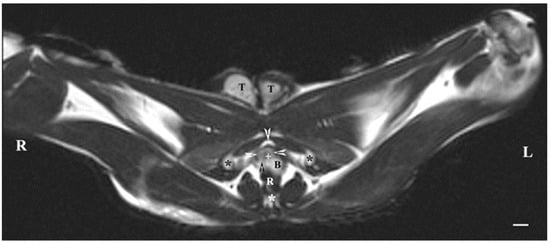

On transverse MRI in a T1-weighted sequence of the pelvis, planes through the following bone anatomical landmarks were used: the first and second caudal vertebrae, dorsally, the caudal part of the pelvic symphysis, ventrally, and the plate of the ischium, laterally. The bulbourethral glands were difficult to identify. They were visualized as soft-tissue, homogeneous findings with an intermediate characteristic compared to the peripheral organs (urethra, rectum, pelvic diaphragm). The shape of the glandular findings was not clearly defined. Each of the glands was imaged independently of the adjacent structures but with indistinct organ boundaries, capsules and parenchyma. The ventromedial pelvic part of the urethra was hypo-intense and visualized dorsally to the caudal part of the pelvic symphysis but without any clear definition of the studied glandular structures. The urethral lumen was hypo-intense relative to the urethral wall. The lumen of the rectum was the most hypo-intense finding compared to the rest of the organs in the perineum (Figure 2 and Figure 3).

Figure 2. T1-weighted transverse image of rabbit pelvis at the level of the first caudal vertebra (black star): R—right; L—left. Bulbourethral glands (white horizontal arrows), the pelvic part of the urethra (black cross), penile bulb and penile root (B), rectum (R), ischial bones (white stars), the caudal part of the pelvic symphysis (white perpendicular arrow), pelvic diaphragm (black perpendicular arrow), and testes (T). Line—10 mm.

Figure 3. T1-weighted transverse image of rabbit pelvis through the level of the second caudal vertebra (white star): R—right; L—left. Bulbourethral glands (white horizontal arrows), the pelvic part of the urethra (white cross), penile bulb (B), rectum (R), ischial bones (black stars), the caudal part of the pelvic symphysis (white perpendicular arrow), pelvic diaphragm (black perpendicular arrow), and testes (T). Line—10 mm.